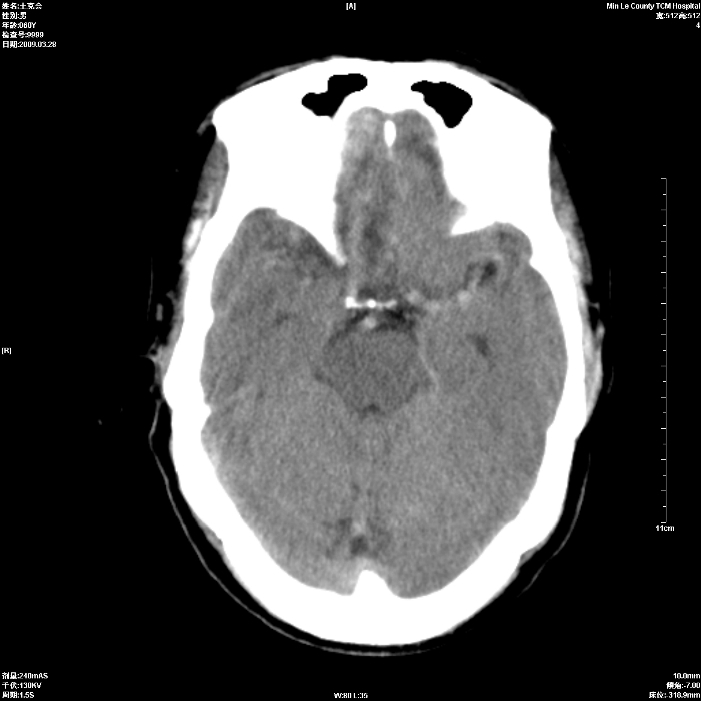

标题: CT19074:患者男60岁头晕头痛一月, [打印本页]

标题: CT19074:患者男60岁头晕头痛一月,

考虑额叶脑转移瘤,建议ct增强

考虑双侧额叶脑转移瘤;建议行进一步检查。

双侧额叶转移瘤

占位征像加水肿带,建议ct增强。

双侧额叶均有低密度影,考虑:1、嗅沟脑膜瘤。2、转移瘤。 建议增强扫描进一步检查。